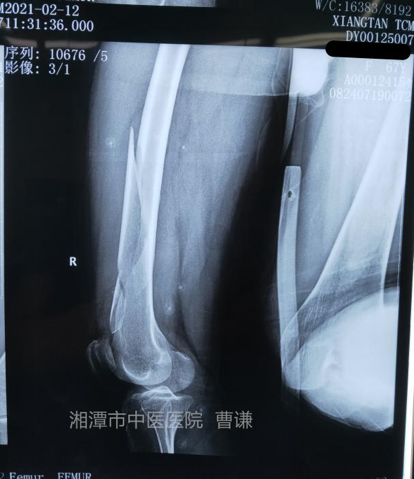

患者女性,67 岁,因外伤致右大腿畸形、肿痛,活动受限就诊于我院。拍片诊断为「右股骨中下段粉碎性骨折」,完善相关检查后行手术治疗。

外伤后拍片示:右股骨中下段粉碎性骨折